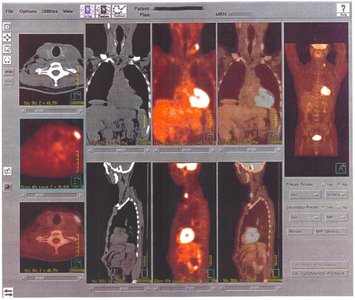

Radioisotopes: Unstable isotopes that emit radiation as they decay; used in medical diagnostics (e.g., PET scans).